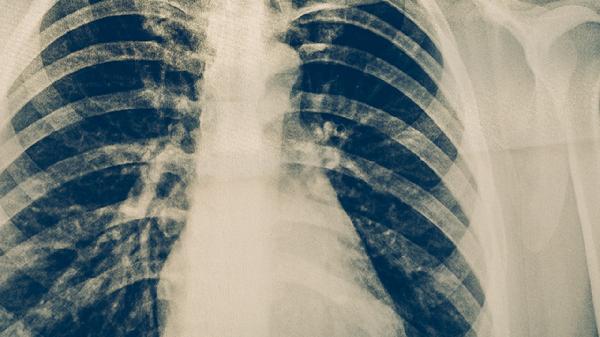

肺結核的癥狀表現(xiàn)主要有咳嗽咳痰、咯血、胸痛、發(fā)熱盜汗、體重下降等。肺結核是由結核分枝桿菌感染引起的慢性傳染病,早期癥狀可能較輕,隨著病情進展癥狀逐漸明顯。

肺結核患者最常見的癥狀是咳嗽咳痰,初期多為干咳,隨著病情發(fā)展可出現(xiàn)黃白色黏痰??人猿掷m(xù)時間較長,通常超過2周,痰中可能帶有血絲。咳嗽咳痰可能與結核分枝桿菌感染導致肺部組織發(fā)生炎癥反應有關。患者可遵醫(yī)囑使用異煙肼片、利福平膠囊、吡嗪酰胺片等抗結核藥物進行治療。

約三分之一的肺結核患者會出現(xiàn)咯血癥狀,表現(xiàn)為痰中帶血或整口咯血??┭潭葟纳倭垦z到大量咯血不等,嚴重時可危及生命??┭赡芘c結核病變侵蝕肺部血管有關。出現(xiàn)咯血癥狀時應立即就醫(yī),醫(yī)生可能會建議使用止血藥物如氨甲環(huán)酸注射液,同時繼續(xù)抗結核治療。

肺結核患者常出現(xiàn)胸部隱痛或刺痛,疼痛多位于病變部位,深呼吸或咳嗽時加重。胸痛可能與結核病變累及胸膜有關?;颊呖勺襻t(yī)囑使用對乙酰氨基酚片緩解疼痛,同時繼續(xù)規(guī)范的抗結核治療如乙胺丁醇片等。

肺結核患者常有午后低熱,體溫多在37.5-38.5℃之間,夜間常伴有盜汗。發(fā)熱盜汗是結核中毒癥狀的表現(xiàn),與結核分枝桿菌感染引起的全身炎癥反應有關?;颊邞⒁庑菹?,補充營養(yǎng),同時遵醫(yī)囑使用抗結核藥物如鏈霉素注射液等。

肺結核患者常出現(xiàn)不明原因的體重下降,可能伴有食欲減退、乏力等癥狀。體重下降與結核感染導致機體消耗增加、營養(yǎng)吸收障礙有關。患者應保證充足營養(yǎng)攝入,多吃高蛋白、高維生素食物,同時堅持規(guī)范的抗結核治療如利福噴丁膠囊等。

肺結核患者應注意保持室內空氣流通,避免與他人密切接觸以防止傳染。保證充足休息,適當進行散步等輕度運動增強體質。飲食上應多攝入雞蛋、牛奶、瘦肉等優(yōu)質蛋白,新鮮蔬菜水果等富含維生素的食物。嚴格遵醫(yī)囑按時服藥,完成全程治療,不可自行停藥。定期復查胸部影像學和痰結核菌檢查,監(jiān)測治療效果。如出現(xiàn)癥狀加重或藥物不良反應,應及時就醫(yī)調整治療方案。